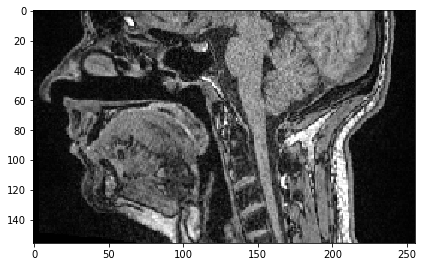

Nous pouvons également sélectionner une sous-région en X. Si nous voulons conserver tous les pixels le long de Z et Y (les deux premières dimensions), nous spécifions simplement : pour tout conserver.

sub_region_x = image[:, :, 100:200]

imshow(sub_region_x[100])

../_images/38728fe7d44860c0fac1767af8007785db40a1042ac2162ae73b3055cddc2023.png